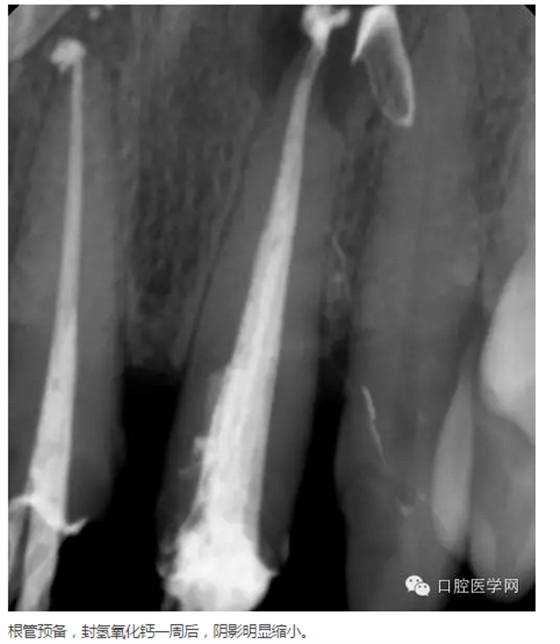

首頁各類病例 左上1根尖膿腫患者

左上1根尖膿腫患者

主訴:上前牙腫痛兩日

現(xiàn)病史:上中切牙疼痛兩日,逐漸加重,自覺唇部腫脹,今來我院求治。

既往史:五年前曾在其他診所鑲過兩顆門牙,具體不詳。

檢查:21相對應(yīng)的前庭溝隆起,粘膜紅腫,有波動感,門診(+),叩(++)。

輔助檢查:21x線示根周有大面積陰影

診斷:21急性根尖周炎

治療方案:建議拆除牙冠,21行根管治療,樁核、全冠修復(fù)